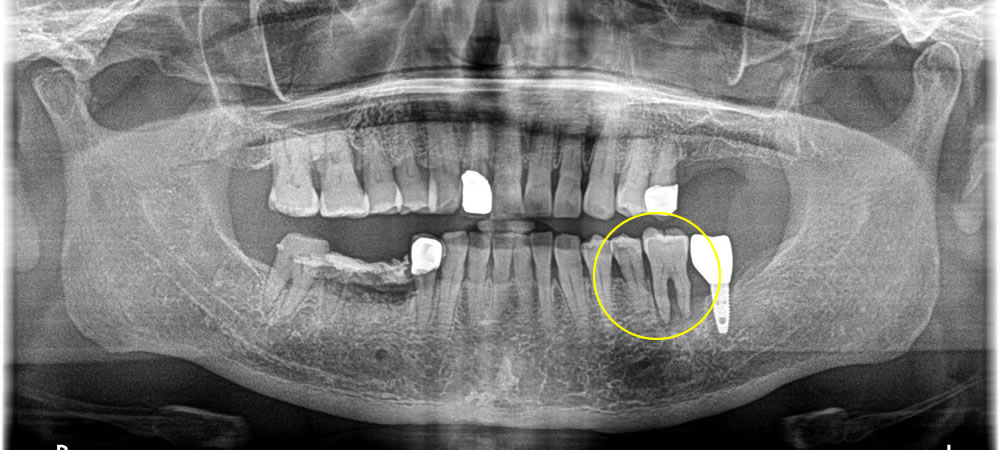

糖尿病に加え、骨も無く他院にてインプラントができないと診断された患者様がどうしても諦めきれないという事で来院されました。

CT検査、口腔内チェックを行い、当院ではインプラントをする事が可能との診断になりました。

抜歯予定である歯を2本抜き、インプラント埋入、骨を作る処置までを1回で行いました。コントロールされてはいるものの、糖尿病を患っているため、術後の感染に対する対策もしっかり行いました。